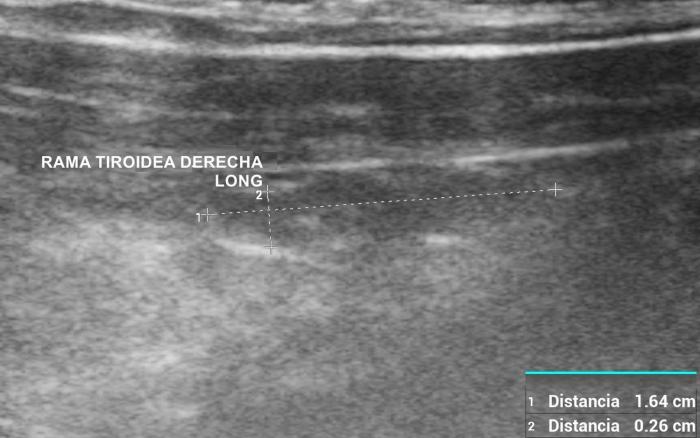

La glándula tiroides en perros y gatos está constituida por dos lóbulos situados a ambos lados de la tráquea cervical, con disposición longitudinal y una forma fusiforme o alargada que se extiende desde el cartílago cricoides hasta la entrada torácica superior2. En condiciones normales, cada lóbulo presenta contornos bien definidos, cápsula hiperecogénica delgada y parénquima homogéneo, con una ecogenicidad generalmente igual o ligeramente superior al músculo esternohioideo adyacente3,8. En la imagen transversal, los lóbulos suelen adoptar una configuración oval o ligeramente triangular (Figura 1); en longitudinal, se observa una forma alargada con extremos redondeados y orientación paralela a los vasos carotídeos y la tráquea1 (Figura 2).

La localización anatómica superficial de la glándula, junto con su estructura relativamente uniforme, facilita su identificación mediante ultrasonografía de alta resolución. Entre los reparos anatómicos más importantes para su localización se encuentran las arterias carótidas comunes (laterales), la tráquea (medial) y los músculos esternotiroideos (ventrales), mientras que el esófago puede constituir una referencia dorsal del lóbulo izquierdo15 (Figuras 3 y 4).

El uso de estructuras vasculares adyacentes como referencias anatómicas ha sido una estrategia útil en ecografía veterinaria para estandarizar las mediciones de órganos pequeños como la glándula tiroides. En este contexto, Bandula Kumara et al. (2019) propusieron la medición de la relación entre el diámetro tiroideo (TD) y el diámetro de la arteria carótida común (CCA) como una forma práctica de evaluar el tamaño de la glándula en perros clínicamente normales (Figura 5A-B).

Los autores realizaron un estudio en el que midieron el diámetro anteroposterior de los lóbulos tiroideos y el diámetro externo de la CCA en cortes transversales obtenidos a nivel del cuello medio. Encontraron que esta relación se mantiene relativamente constante entre razas y tamaños corporales, sugiriendo que puede ser utilizada como parámetro de referencia ecográfica. Específicamente, en perros adultos sanos, la relación TD/CCA fue de 1.74 ± 0.40 (rango 1.11–2.43)6. Si los valores se encuentran por debajo del rango normal pueden ser considerados potencialmente indicativos de hipoplasia tiroidea o atrofia glandular.

Una ventaja de esta relación es que la arteria carótida común es fácilmente identificable ecográficamente, presenta un diámetro estable y poco variable en condiciones fisiológicas, y se ubica en estrecha proximidad con la glándula tiroides. Esto la convierte en una excelente estructura de referencia para normalizar mediciones entre individuos de diferente tamaño corporal, permitiendo evaluaciones objetivas en poblaciones mixtas de perros de compañía.